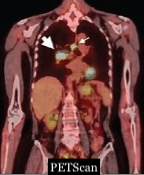

Une étude japonaise publiée dans l’American Journal of Roentgenology (AJR) montre les apports de l’IRM et du PET/IRM dans le diagnostic du cancer du poumon. Ce travail démontre la grande précision des résultats qu’ils obtiennent pour évaluer la taille des lésions et la stadification de la maladie.

Selon un article paru dans l'American Journal of Roentgenology (AJR), l'IRM, avec ou sans une fusion au FDG PETScan, peut améliorer la stadification des patients atteints d'un cancer du poumon à petites cellules (CPPC).

« Le PETScan au FDG, l'IRM du corps entier et la TEP/IRM au FDG fusionnés ont surpassé les examens conventionnels pour divers paramètres de stadification chez les patients atteints de Cancer du poumon à petites cellules, commente le premier auteur de cette étude,

le Dr Yoshiharu Ohno de la faculté de médecine de l'Université de santé Fujita au Japon. L'IRM du corps entier et la PET/IRM au FDG s’avèrent meilleurs que le PETScan au FDG, notamment pour évaluer la taille des lésions et l'étendue de l'invasion locale dans le CPPC ».

Chez les patients atteints de CPPC, la précision de la taille des lésions était plus élevée pour l'IRM corps entier (94,9 %) et la PET/IRM au FDG (94,9 %) que pour le PETScan au FDG (85,7 %). D’autre part, la précision de la stadification selon l’échelle TNM était plus élevée pour l'IRM corps entier (88,8%) et la FDG PET/IRM (86,7%) que pour le FDG PETScan (77,6%) et les examens de stadification conventionnels (72,4%).